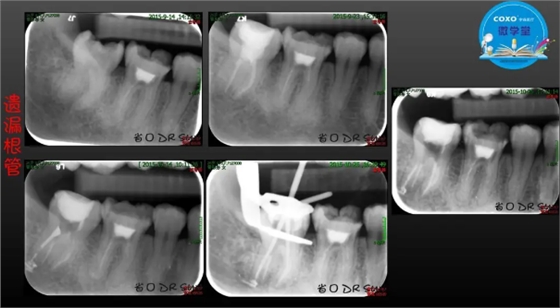

主讲:孙书昱

主任医师,牙体牙髓副主任, 广东省口腔医院牙体牙髓科 主任医师。2003年硕士研究生毕业,研究方向为牙体牙髓病学,擅长于牙体牙髓病的诊断、龋齿、牙髓炎、根尖周病的治疗以及前牙美容修复。